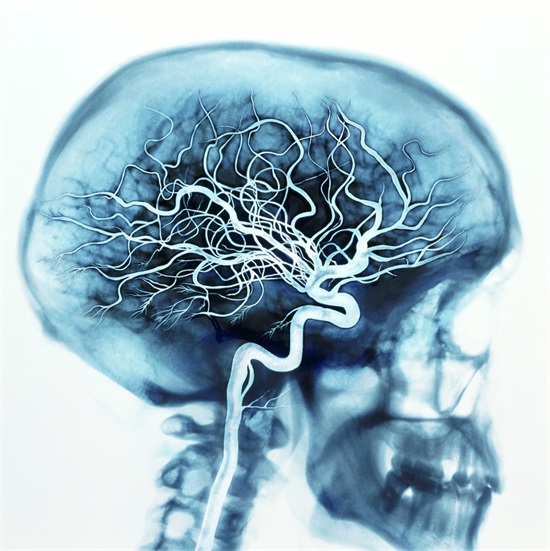

脑袋被砍掉后,血压瞬间消失,但大脑毛细血管中仍然会存在大量血液,组织中也存在溶解氧和血液,能为大脑提供部分时间。

这个问题牵扯出了人体的意识,因为只有意识所在部分才能体现谁才是身体的主体,很显然我们人体的意识所在位置是大脑。

当脑袋被砍掉时,脑袋会觉得自己滚落了,并且此时还会有痛觉,毕竟大脑就是身体的中枢神经,在大脑缺氧死亡之前,他都会有这个感觉!

所以在脑袋掉落的瞬间,会有痛觉、跌落的感觉和缺氧的眩晕感,嘴巴和鼻子以及眼睛功能都保持正常,只是没有肺部连接,嘴巴和鼻子都不再具有功能。